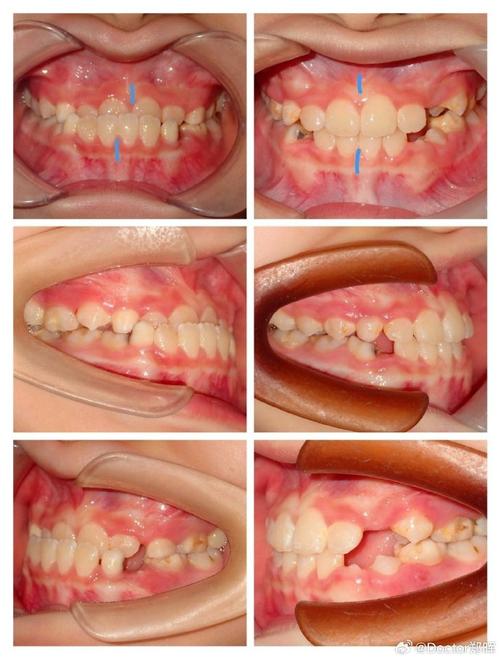

反颌 (Malocclusion - Crossbite)

- 定义: 反颌是一种常见的错颌畸形,指的是下颌牙齿(下牙弓)相对于上颌牙齿(上牙弓)位于更靠前的位置,通俗地说,就是俗称的“地包天”或“兜齿”。

- 前牙反颌: 最常见,上前牙咬合在下前牙的舌侧(里面),这会导致面中部凹陷,下巴前突(小下巴),侧貌呈“月牙形”或“猿猴状”。

- 后牙反颌: 下后牙咬合在上后牙的颊侧(外面),这会导致面下1/3宽度不对称,可能影响咀嚼功能和颞下颌关节。

偏颌 (Malocclusion - Facial Asymmetry / Mandibular Deviation)

- 定义: 偏颌是指面部左右两侧明显不对称,通常表现为下颌骨(下巴)相对于面部中线向一侧偏移或旋转,这种不对称可以是骨骼性的,也可以是牙齿性的,或者两者兼有。

- 中线偏斜: 上下牙列的中线不一致,或与面部中线不一致。

- 下颌偏斜: 下巴尖向左或向右偏移。

- 颏点偏移: 下巴最前点偏离面部中线。

- 面部不对称: 两侧面颊、下颌角、耳屏前区等高度或宽度不一致,笑时更明显。